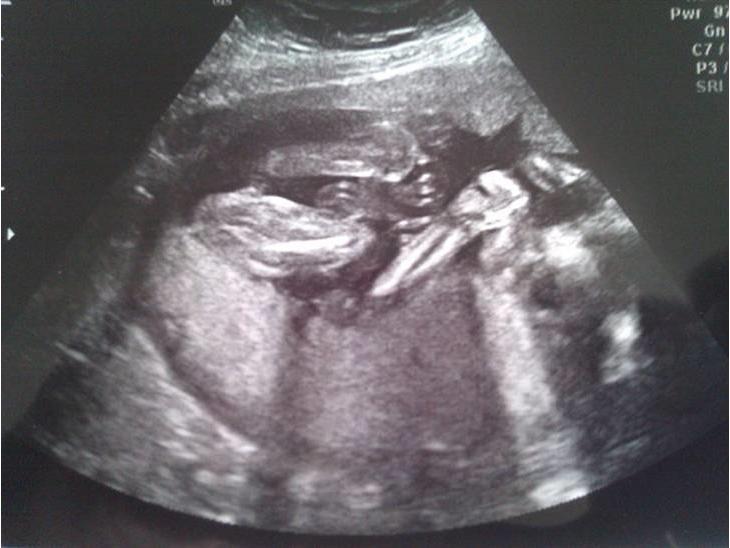

Køns scanning (Mille)

Betalte os fra en extra 20 ugersscanning da de på sygehuset ikk var sikre på det var en lille pige som var på vej.